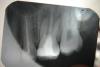

Дата первых двух фотографий - 26.02.2010, дата снимка на третьей - 19.08.2008

Нарыв образовался в сентябре 2007го после неаккуратного обращения с зубной щёткой (ударила пластиковым корпусом) и до сих пор живёт своей жизнью. Регулярно то увеличивается, то уменьшается. Когда слишком много гноя, придавливаю - выходит. Всякие мази и примочки - пройденный этап, бесполезно. По снимку врач сказала, что это свич(прямо из корня), и что всё само пройдёт, когда раскрыть зуб и несколько дней пролечить изнутри. Продолжить лечение не получилось из-за работы, а дальше просто затянула, натура такая нехорошая всё делать в последний момент...

Зубная щетка не имеет отношения к образованию свища. И само не пройдет, а пройдет, если хороший профессионал хорошенько потрудится, зуб не самый простой. И если все получится, то закрепите успех восстановив зуб культевой вкладкой и коронкой.